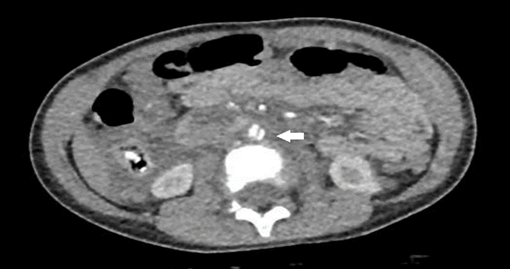

Patient S.C.D.M., a 3-year-old male, was brought by emergency medical transport after a high-speed car rollover. He was admitted hemodynamically stable, on an oxygen mask, with a Glasgow Coma Scale score of 14, opening his eyes upon being called and reporting diffuse abdominal pain. Physical examination revealed a distended abdomen with ecchymosis in the pelvic region consistent with the seat belt sign. After clinical stabilization, he underwent a contrast-enhanced abdominal tomography (CT scan), which identified a normal-sized abdominal aorta with parietal irregularities resembling a dissection flap in the infrarenal segment and at the emergence of the right common iliac artery, suggestive of areas of dissection (Figure 1). There were no signs of intravenous contrast extravasation into the peritoneal cavity. The abdominal aorta measured approximately 5.6 mm before the dissection and 8 mm in the dissected infrarenal region with the false lumen (Figure 2). The lesion was classified as a Stanford type B aortic dissection.

Figure 1: Contrast-enhanced abdominal tomography that identified the abdominal aorta presenting parietal irregularities with a dissection flap appearance in the infrarenal segment (arrow), with no signs of intravenous contrast extravasation into the peritoneal cavity.